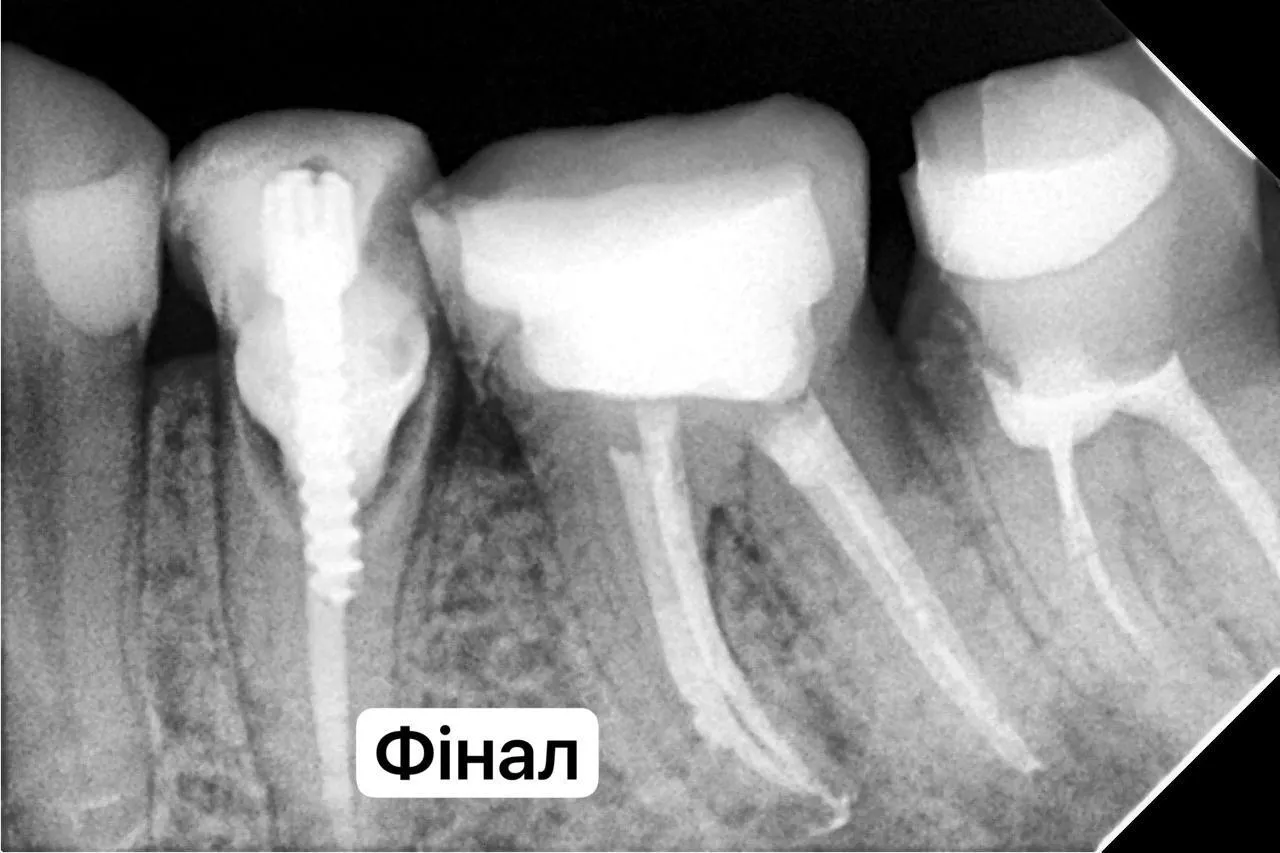

Вторинне ендо зуба 36 + підготовка